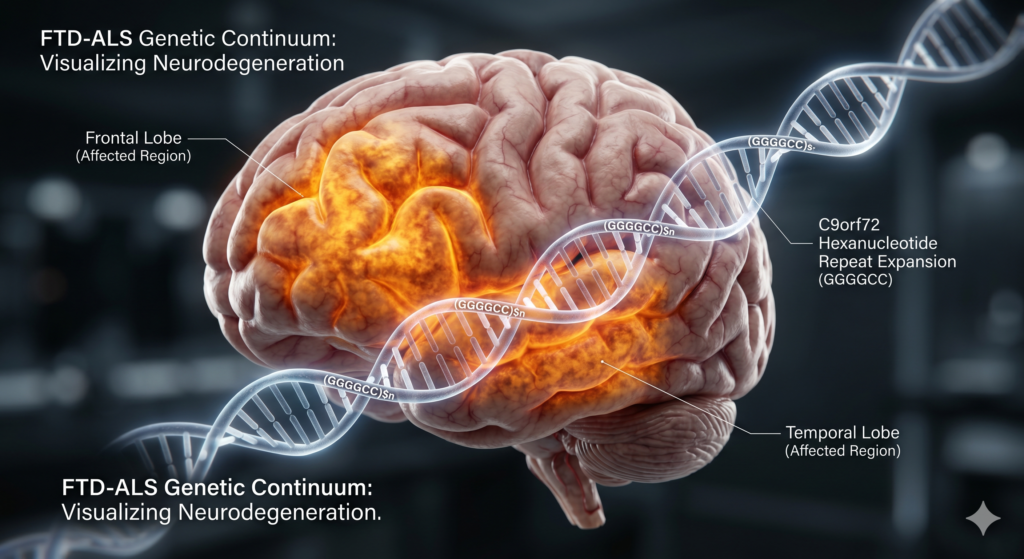

دمانس فرونتوتمپورال

تحلیل جامع و تحولآفرین در قلمرو دمانس فرونتوتمپورال و پیوستار ژنتیکی با ALS تحلیل جامع و تحولآفرین در قلمرو دمانس فرونتوتمپورال و پیوستار ژنتیکی با ALS از متدولوژی MTAG تا پارادایمهای نوین در پزشکی دقیق و راهبردهای مراقبتی درک مدرن از بیماریهای تخریبکننده عصبی (Neurodegenerative Diseases) به سرعت از مدلهای طبقهبندی ساده بر اساس علائم […]